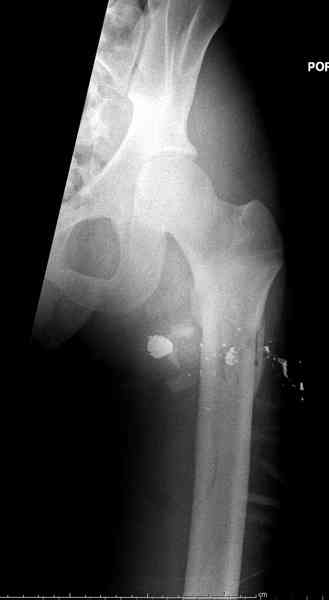

В нашем случае 21 летний боец уличного фронта, фиксацию провели на следующий день, зафиксирован интрамедуллярным штифтом. Не стали делать первичную хирургическую обработку точечной раны, зафиксирован как есть. Клинические снимки: